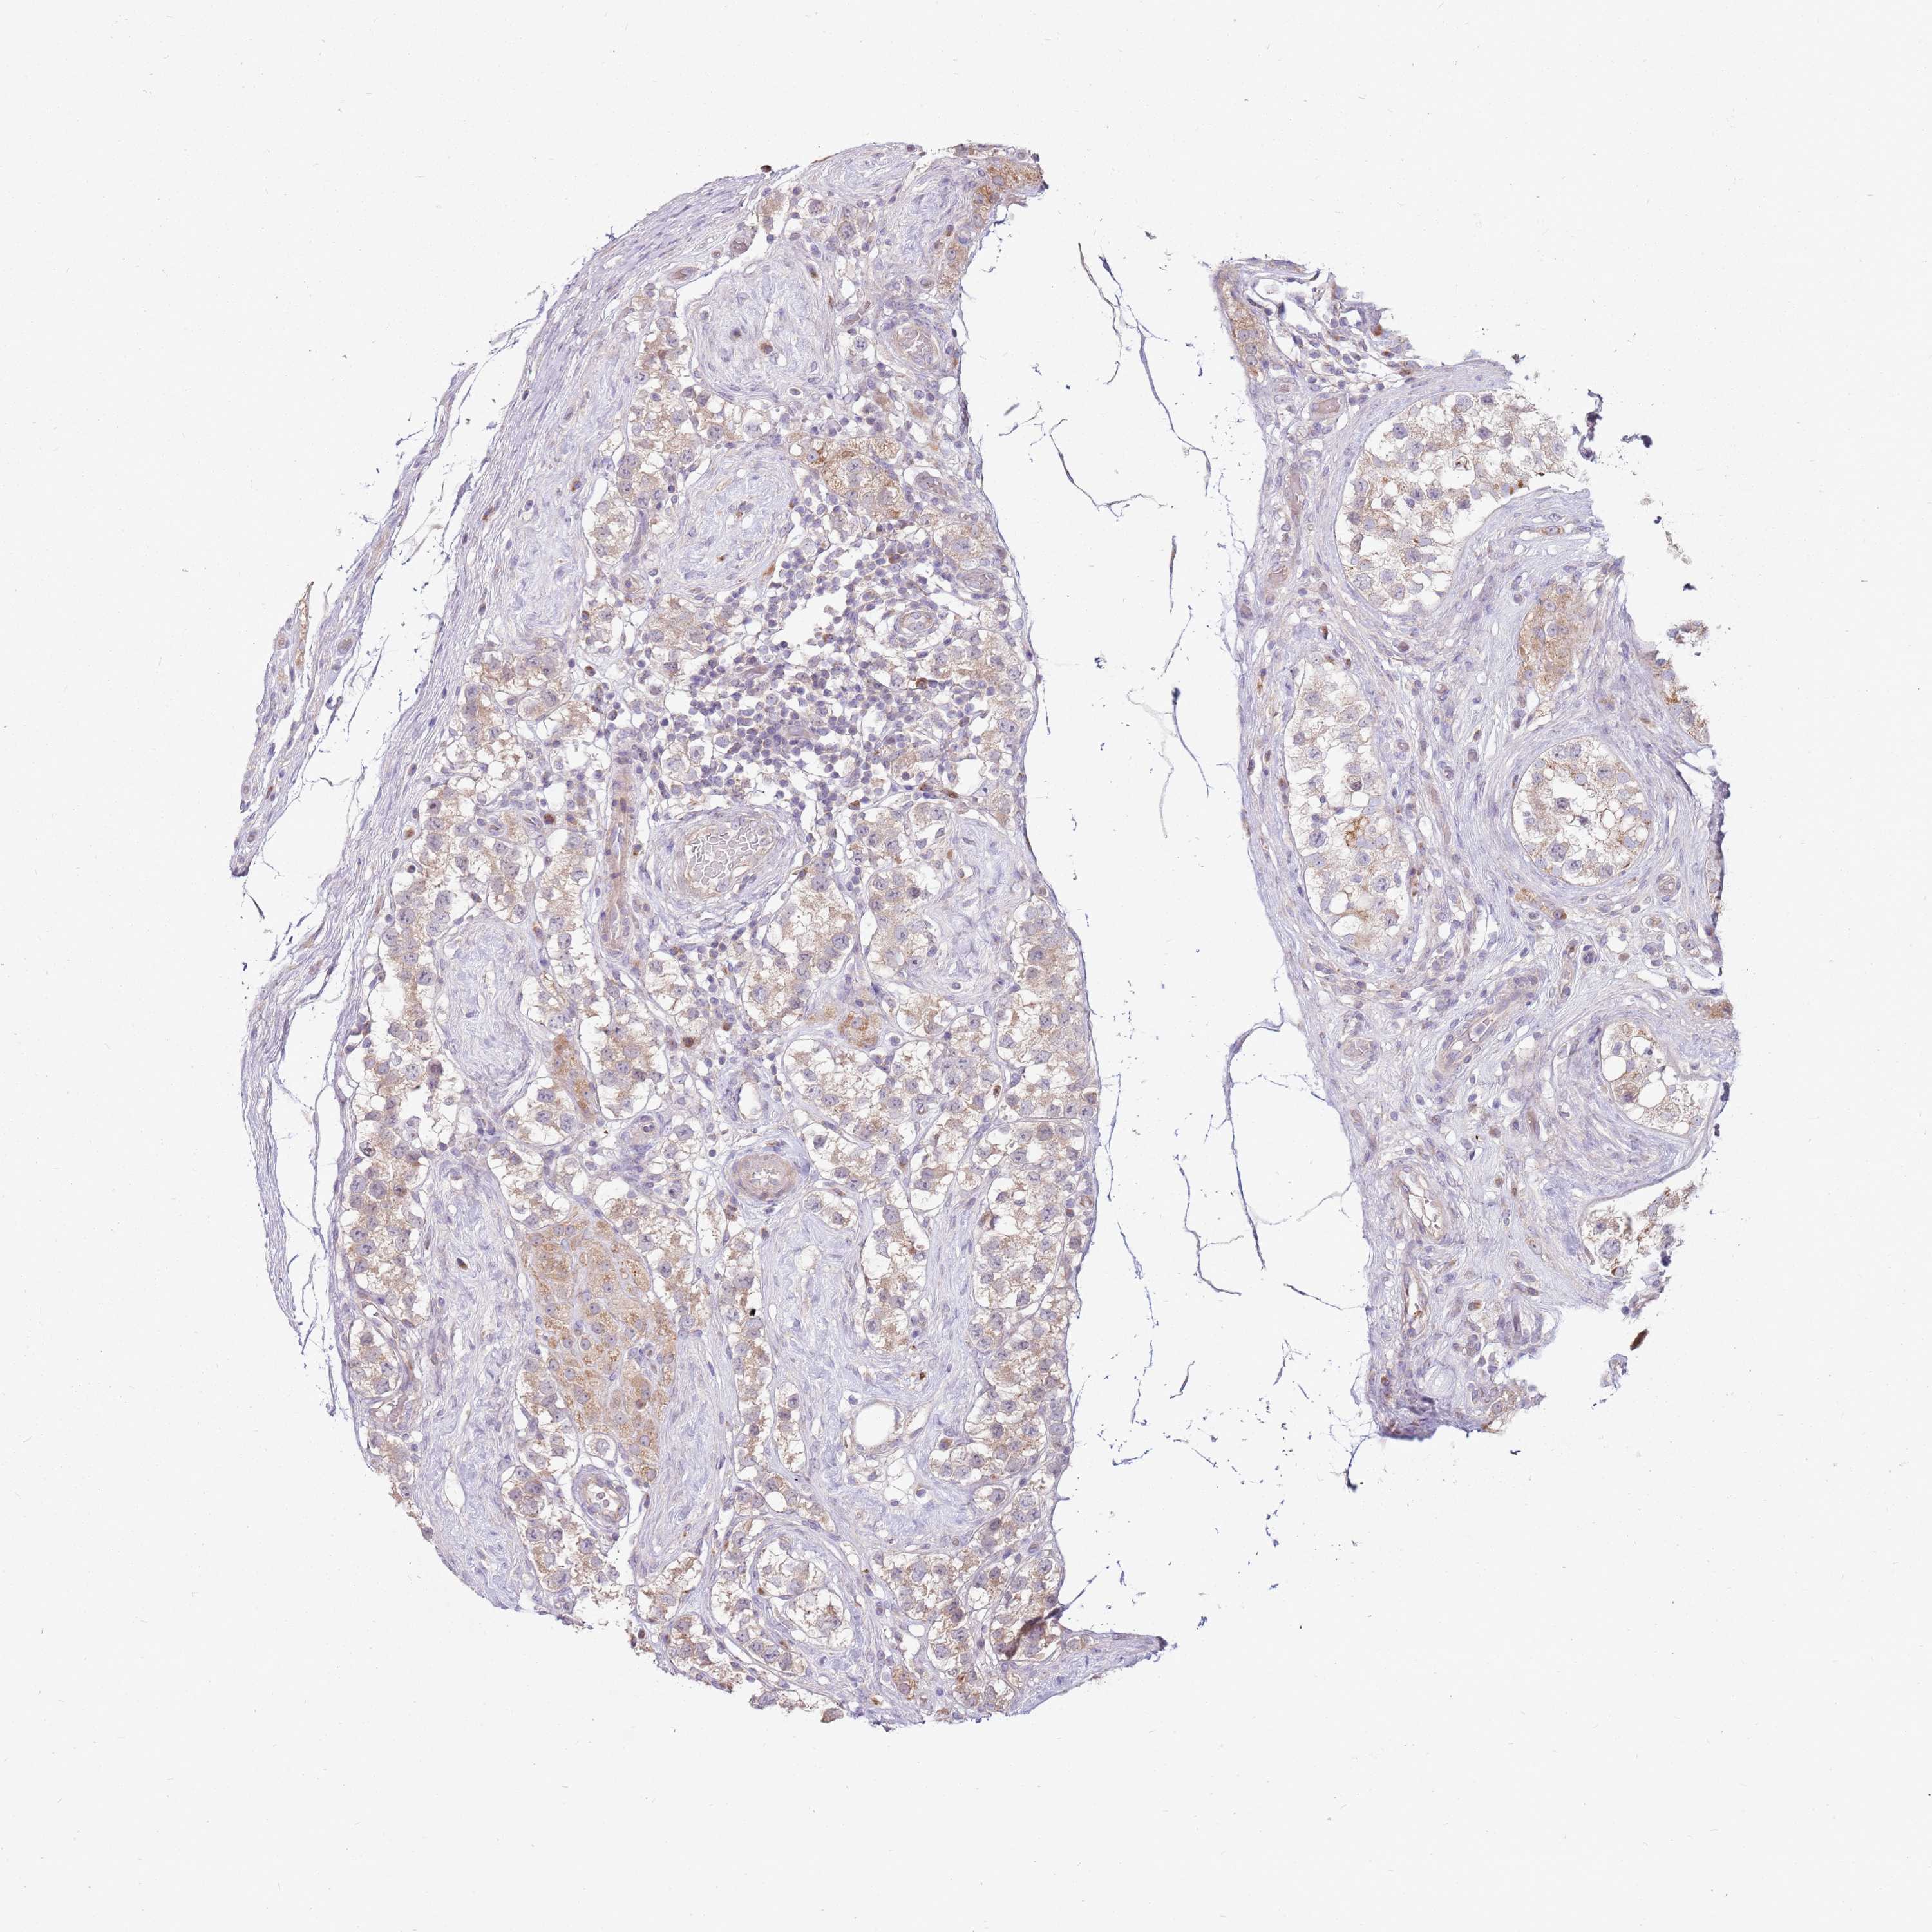

TESTIS CANCER - Protein expressioni

A mouse-over function shows sample information and annotation data. Click on an image to view it in a full screen mode. Samples can be filtered based on level of antibody staining by selecting one or several of the following categories: high, medium, low and not detected. The assay and annotation is described here.

Note that samples used for immunohistochemistry by the Human Protein Atlas do not correspond to samples in the TCGA dataset.

Antibody stainingi

Antibody staining in the annotated cell types in the current human tissue is reported as not detected, low, medium, or high, based on conventional immunohistochemistry profiling in selected tissues. This score is based on the combination of the staining intensity and fraction of stained cells.

Each image is clickable and will lead to virtual microscopy that enables deeper exploration of all samples and also displays staining intensity scores, fraction scores and subcellular localization as well as patient and tissue information for each sample.

Antibody HPA048923

Staining

High

Medium

Low

Not detected

Intensity

Strong

Moderate

Weak

Negative

Quantity

>75%

75%-25%

<25%

None

Location

Nuclear

Cytoplasmic/membranous

Cytoplasmic/membranous,nuclear

Carcinoma, Embryonal, NOS

Seminoma, NOS

Urothelial carcinoma, High grade